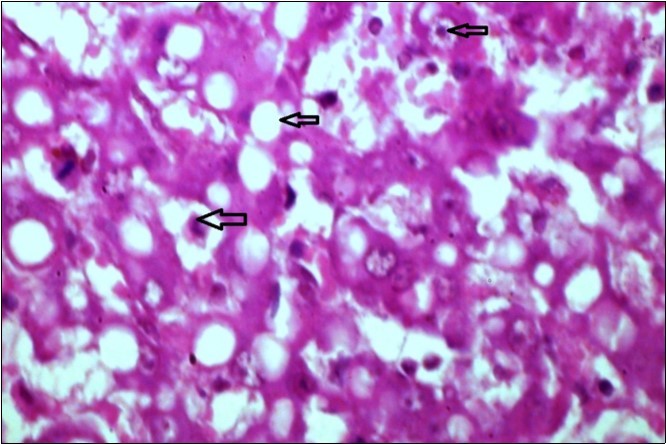

Figure 12.liver (dead cattle less than 1 year old) showed hepatocytes suffering hydropic degeneration. And necrosis (H&E, X 60).

liver (dead cattle less than 1 year old) showed hepatocytes suffering hydropic degeneration. And necrosis  (H&E, X 60).